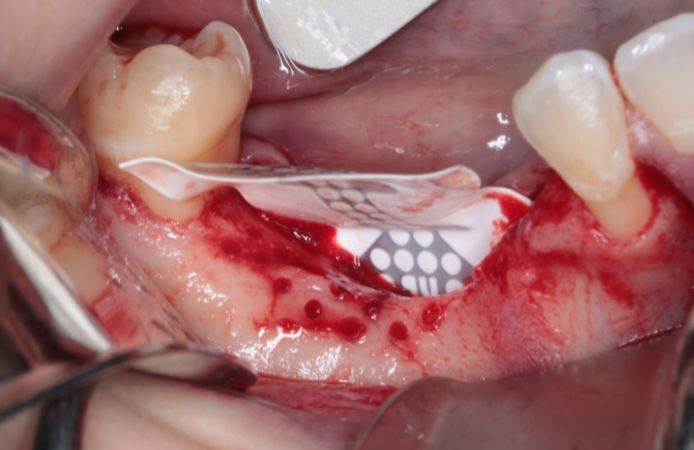

Figure 3.

Bone defect visible after full thickness flap elevation. A mid-crestal incision was performed with intrasulcular incisions. Vertical incisions were performed one tooth away from the defect.

Figure 4.

The site was prepared with bone perforation. A NeoGen Ti-Reinforced PTFE Membrane was inserted and fixed lingually with two screws. The titanium-reinforced membrane provides structural support for space maintenance and undisturbed bone regeneration.